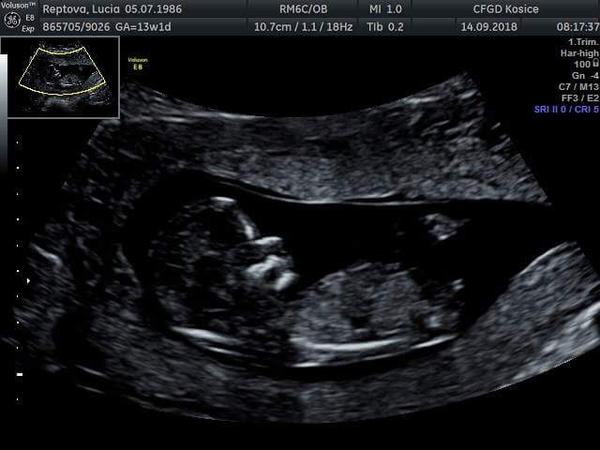

Žienky, ako vyzerajú vaše dvojičky na sone? Máte už fotku? 🙂

My sme boli stvrtok na sone, koniec 12 tyzdna